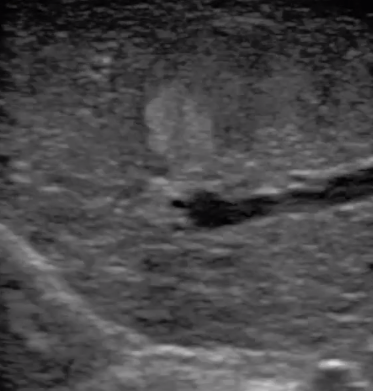

腹腔鏡超聲是超聲技術(shù)和腹腔鏡技術(shù)的融合,腹腔鏡超聲降低了對超聲探測深度的要求。由微小切口進(jìn)入手術(shù)部位,多角度彎曲可選擇,降低手術(shù)難度及風(fēng)險;與受檢組織器官直接接觸,有效避免氣體干擾。

應(yīng)用科室:麻醉科、手術(shù)室、普外科、泌尿外科、婦產(chǎn)科、腫瘤科、介入科等

腹腔鏡下 肝臟占位